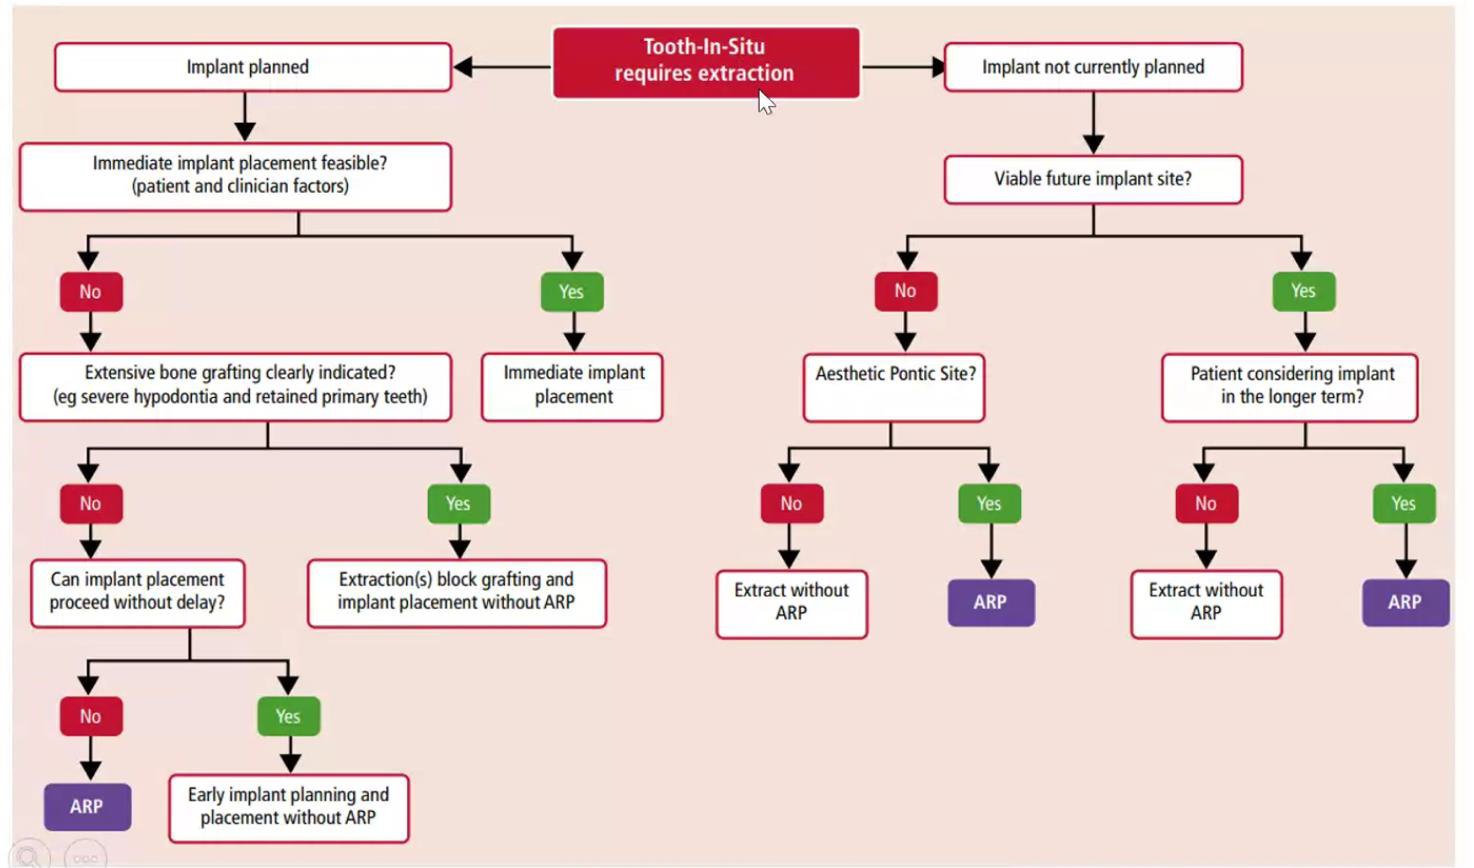

ARP 決策樹